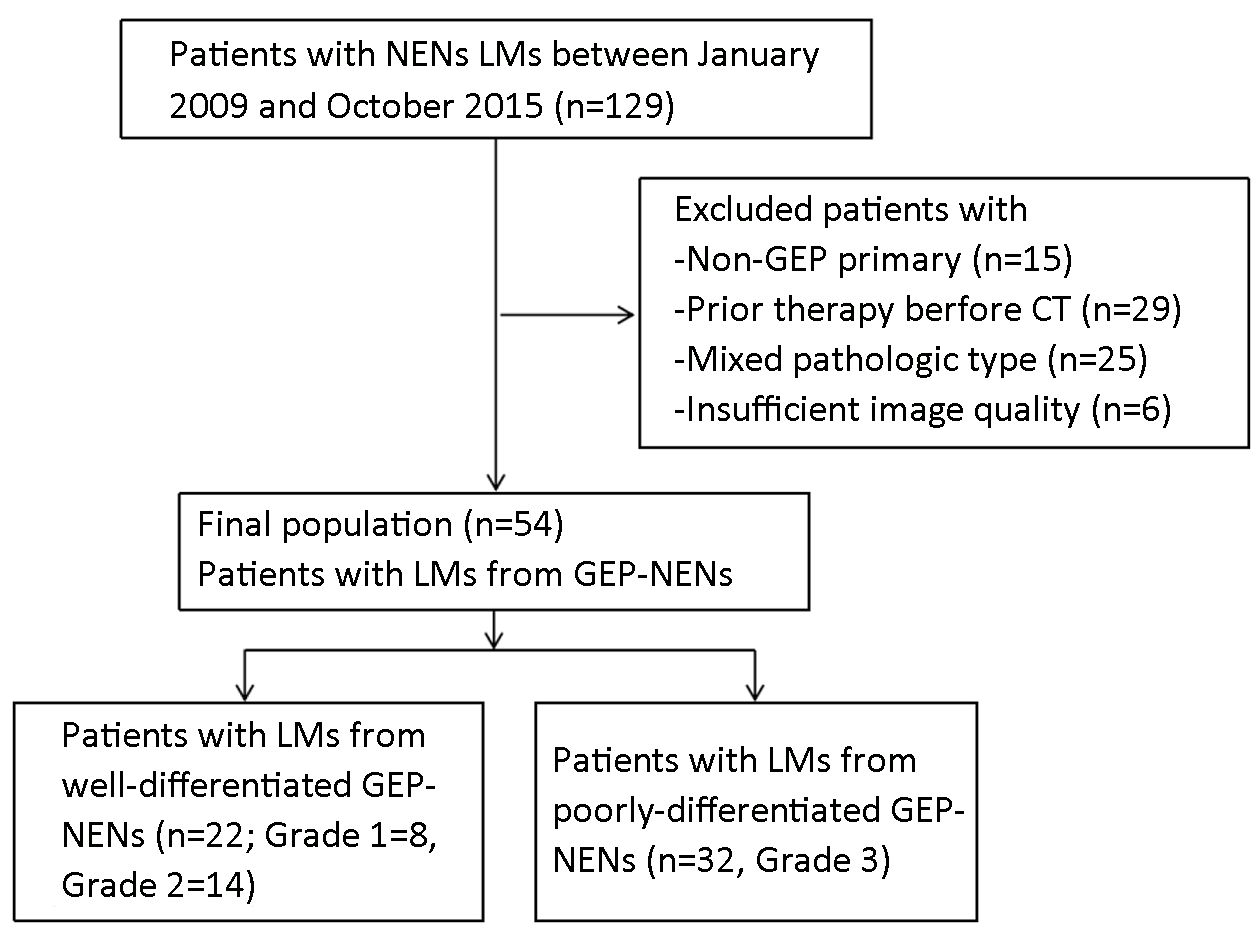

A total of 129 patients with pathologically proven NEN LMs who had undergone CT examination were identified in Peking University Cancer Hospital during the study period. Of these patients, 54 fulfilled the inclusion criteria and were enrolled in the study (Figure 1). The clinical characteristics of the patients are listed in Table 1.